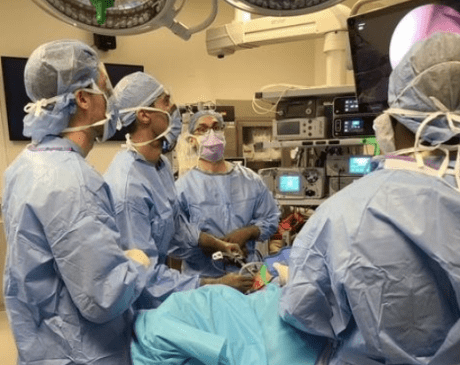

Dr. Stein specializes in arthroscopic surgery of the shoulder, knee, elbow, and ankle. This includes arthroscopic shoulder rotator cuff repairs, labral repairs, and shoulder stabilization procedures. His knee expertise includes arthroscopic ligament reconstructions, meniscus repair, tendon repairs, and cartilage procedures.

Dr. Stein was on the teaching faculty at New York University Langone Medical Center as an assistant clinical professor and teaches residents in the operating room. He also is on the assistant faculty for national education for the Arthroscopy Association of North America (AANA) and assists in teaching surgical skills to residents from around the country. He was on national committees for the AANA.

Dr. Stein specializes in arthroscopic surgery of the shoulder, knee, elbow, and ankle. This includes arthroscopic shoulder rotator cuff repairs, labral repairs, and shoulder stabilization procedures. His knee expertise includes arthroscopic ligament reconstructions, meniscus repair, tendon repairs, and cartilage procedures.

Dr. Stein was on the teaching faculty at New York University Langone Medical Center as an assistant clinical professor and teaches residents in the operating room. He also is on the assistant faculty for national education for the Arthroscopy Association of North America (AANA) and assists in teaching surgical skills to residents from around the country. He was on national committees for the AANA.